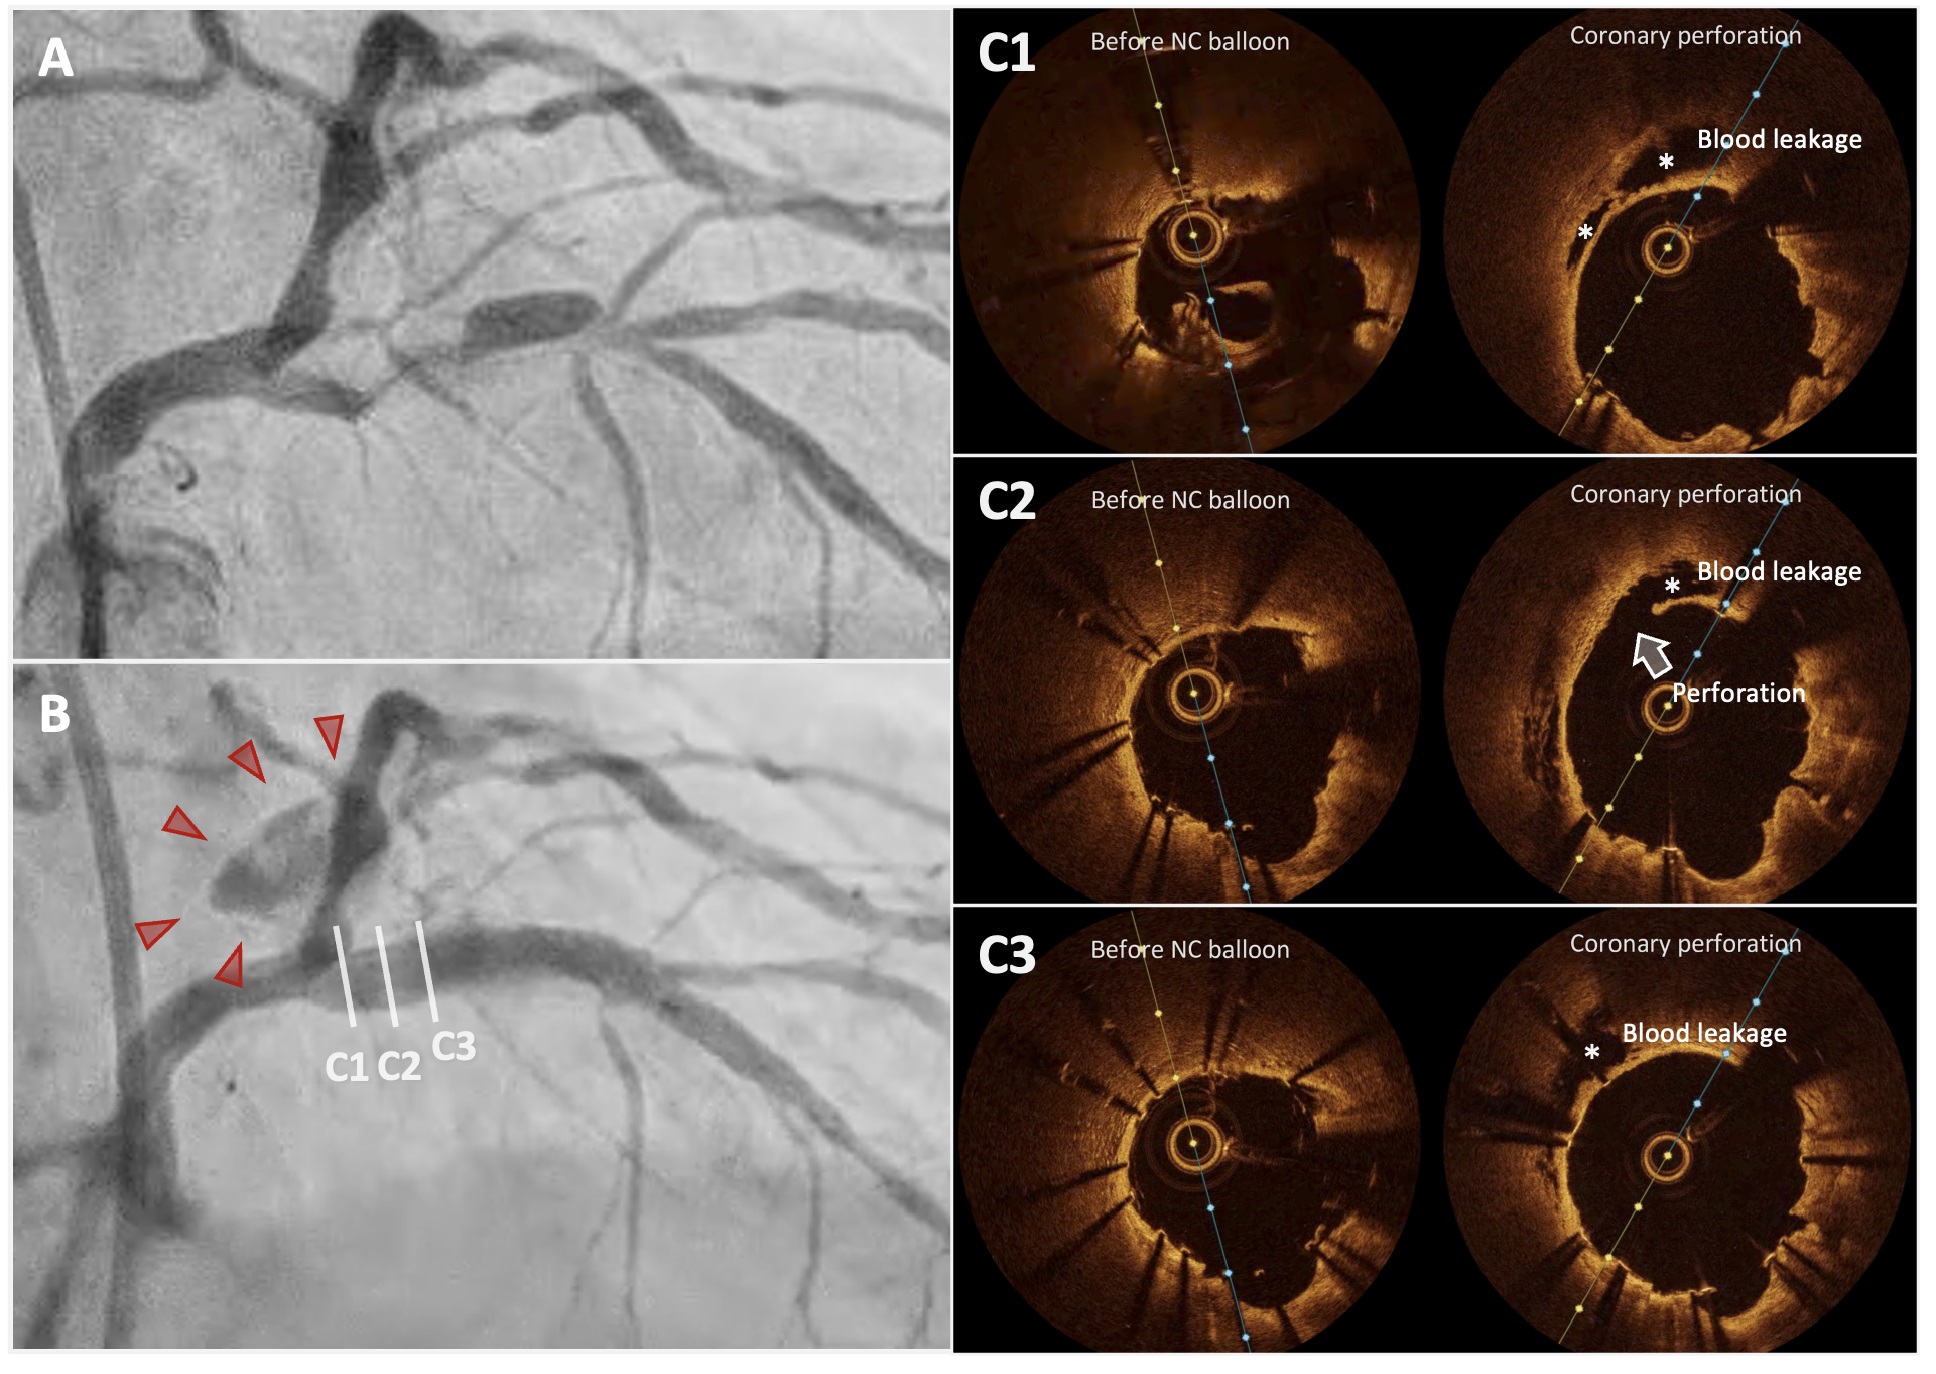

Coronary angiography revealed severe, heavily calcified stenosis in the proximal LAD. After stent implantation, OCT showed marked incomplete stent apposition at the proximal segment. During the OCT run, contrast extravasation emerged at the stent¡¯s proximal edge, indicating perforation.

Lesion preparation was performed with rotational atherectomy (1.5mm burr) and 3.0mm balloon predilation were performed, followed by implantation of a 3.0¡¿32mm Synergy drug-eluting stent (DES) in the proximal LAD. Post-stent OCT demonstrated notable incomplete stent apposition, so post-dilation with a 4.0-mm non-compliant balloon was undertaken, focusing on the proximal portion. During the subsequent OCT angiography run, new contrast extravasation was seen at the proximal stent edge consistent with coronary perforation. Immediate inflation of a 3.5-mm perfusion balloon across the injured segment secured hemostasis while maintaining distal flow. Extravascular hemorrhage gradually subsided, and the patient remained hemodynamically stable. Comparative OCT frames before and after the event revealed epicardial-side wall detachment and signal-free zones within perivascular adipose tissue. Notably, pre-dilation OCT at the same site showed loss of the normal three-layer architecture, suggesting local fragility that, combined with aggressive post-dilation in a calcified segment, predisposed the vessel to perforation.

OCT revealed the mechanism of perforation and its warning signs. These include wall detachment and extravascular signal loss at the perforation site, as well as pre-existing weakening of the arterial tri-laminar structure at the injury site. Recognizing these patterns may allow for more cautious post-dilatation management during the use of debulking devices for calcified coronary lesions.